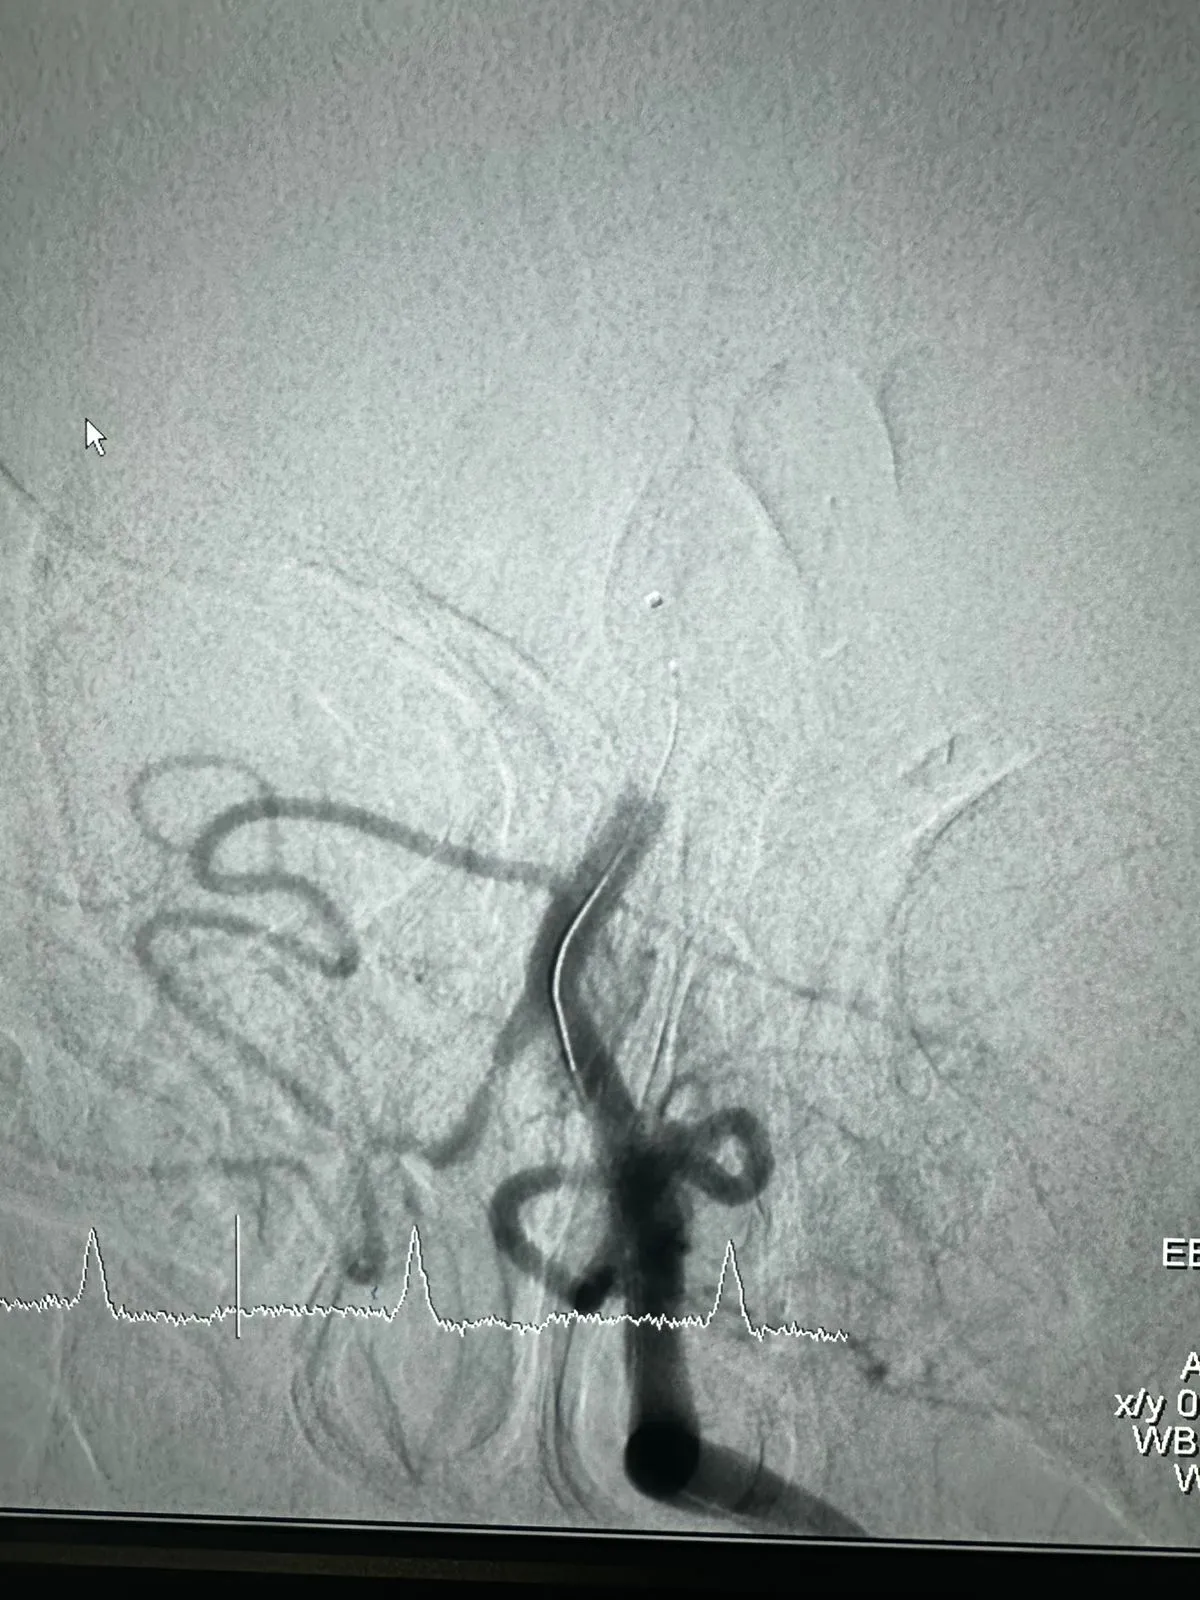

Niedawno miał miejsce udany przypadek trombektomii z użyciem urządzenia Dredger Stent Retriever firmy NeuroSafe Medical Co., Ltd. Urządzenie Dredger Stent Retriever ma nieinwazyjną, miękką końcówkę, która znacznie zmniejsza ryzyko uszkodzenia błony wewnętrznej, a także specjalny kształt otworu, który wychwytuje skrzepy krwi głównie poprzez zaciskanie zmian szczeliny.